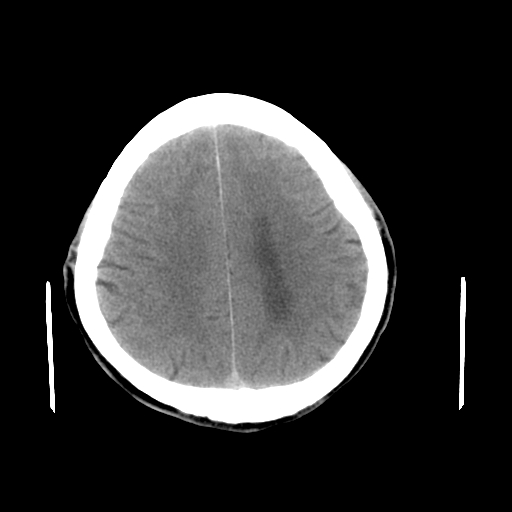

男,64岁,左侧肢体活动障碍两天。

轻度髓质脑萎缩,建议定期复查。

脑萎缩.

脑萎缩

考虑 脑萎缩,脑积水待排